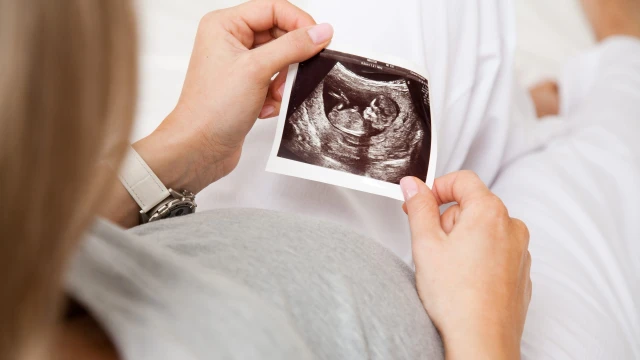

Kết quả đo độ mờ da gáy cao nhưng chọc ối bình thường có thể xảy ra trong một số trường hợp. Việc đo độ mờ da gáy chỉ cung cấp thông tin một phần, và đôi khi nó có thể không phản ánh đúng tình hình của thai nhi. Trong trường hợp này, bác sĩ sẽ tiếp tục theo dõi và đánh giá sự phát triển của thai nhi bằng cách sử dụng kết quả chọc ối để đưa ra đánh giá tổng quan về tình hình sức khỏe của thai nhi. Hãy cùng Nhà thuốc Long Châu tìm hiểu về trường hợp này nhé!